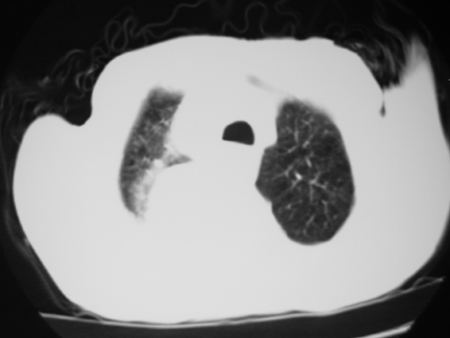

男77岁,胸痛就诊

右侧胸腔积液,部分包裹,右下肺膨胀不全,右下肺感染。

右侧胸腔积液,部分包裹,右下肺膨胀不全

右侧胸腔积液,部分包裹,右下肺膨胀不全,右下肺感染